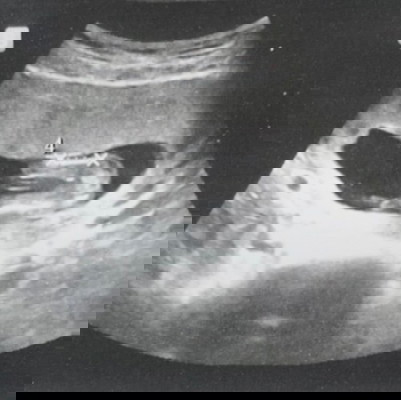

รบกวนเเม่ๆ ช่วยดูใบซาวน์ให้หน่อยค่ะ เพศอะไร😊🙏

วันนี้ไปซาวน์น้องมา อายุครรภ์15สัปดาห์เเล้วค่ะ ถามเพศหมอ หมอบอกให้รอซาวน์ครั้งหน้า เลยอยากให้เเม่ช่วยดูหน่อยค่ะ

ลูกสาวคะ ถ้าเห็นยากๆ เพราะถ้าเป็นลูกชาย จู๋ยะโผล่ให้เห็นละ

น่าจะผู้หญิงค่ะ ถ้าอยากเห็นชัดๆรอ. 20wขึ้นไปค่ะเเม่

น่าจะผู้หญิงนะคะ ถ้าผู้ชายจะมีพุ่งออกมาแบบนี้คะ

เหมือนจะหญิงนะเป็นกลีบเชียว